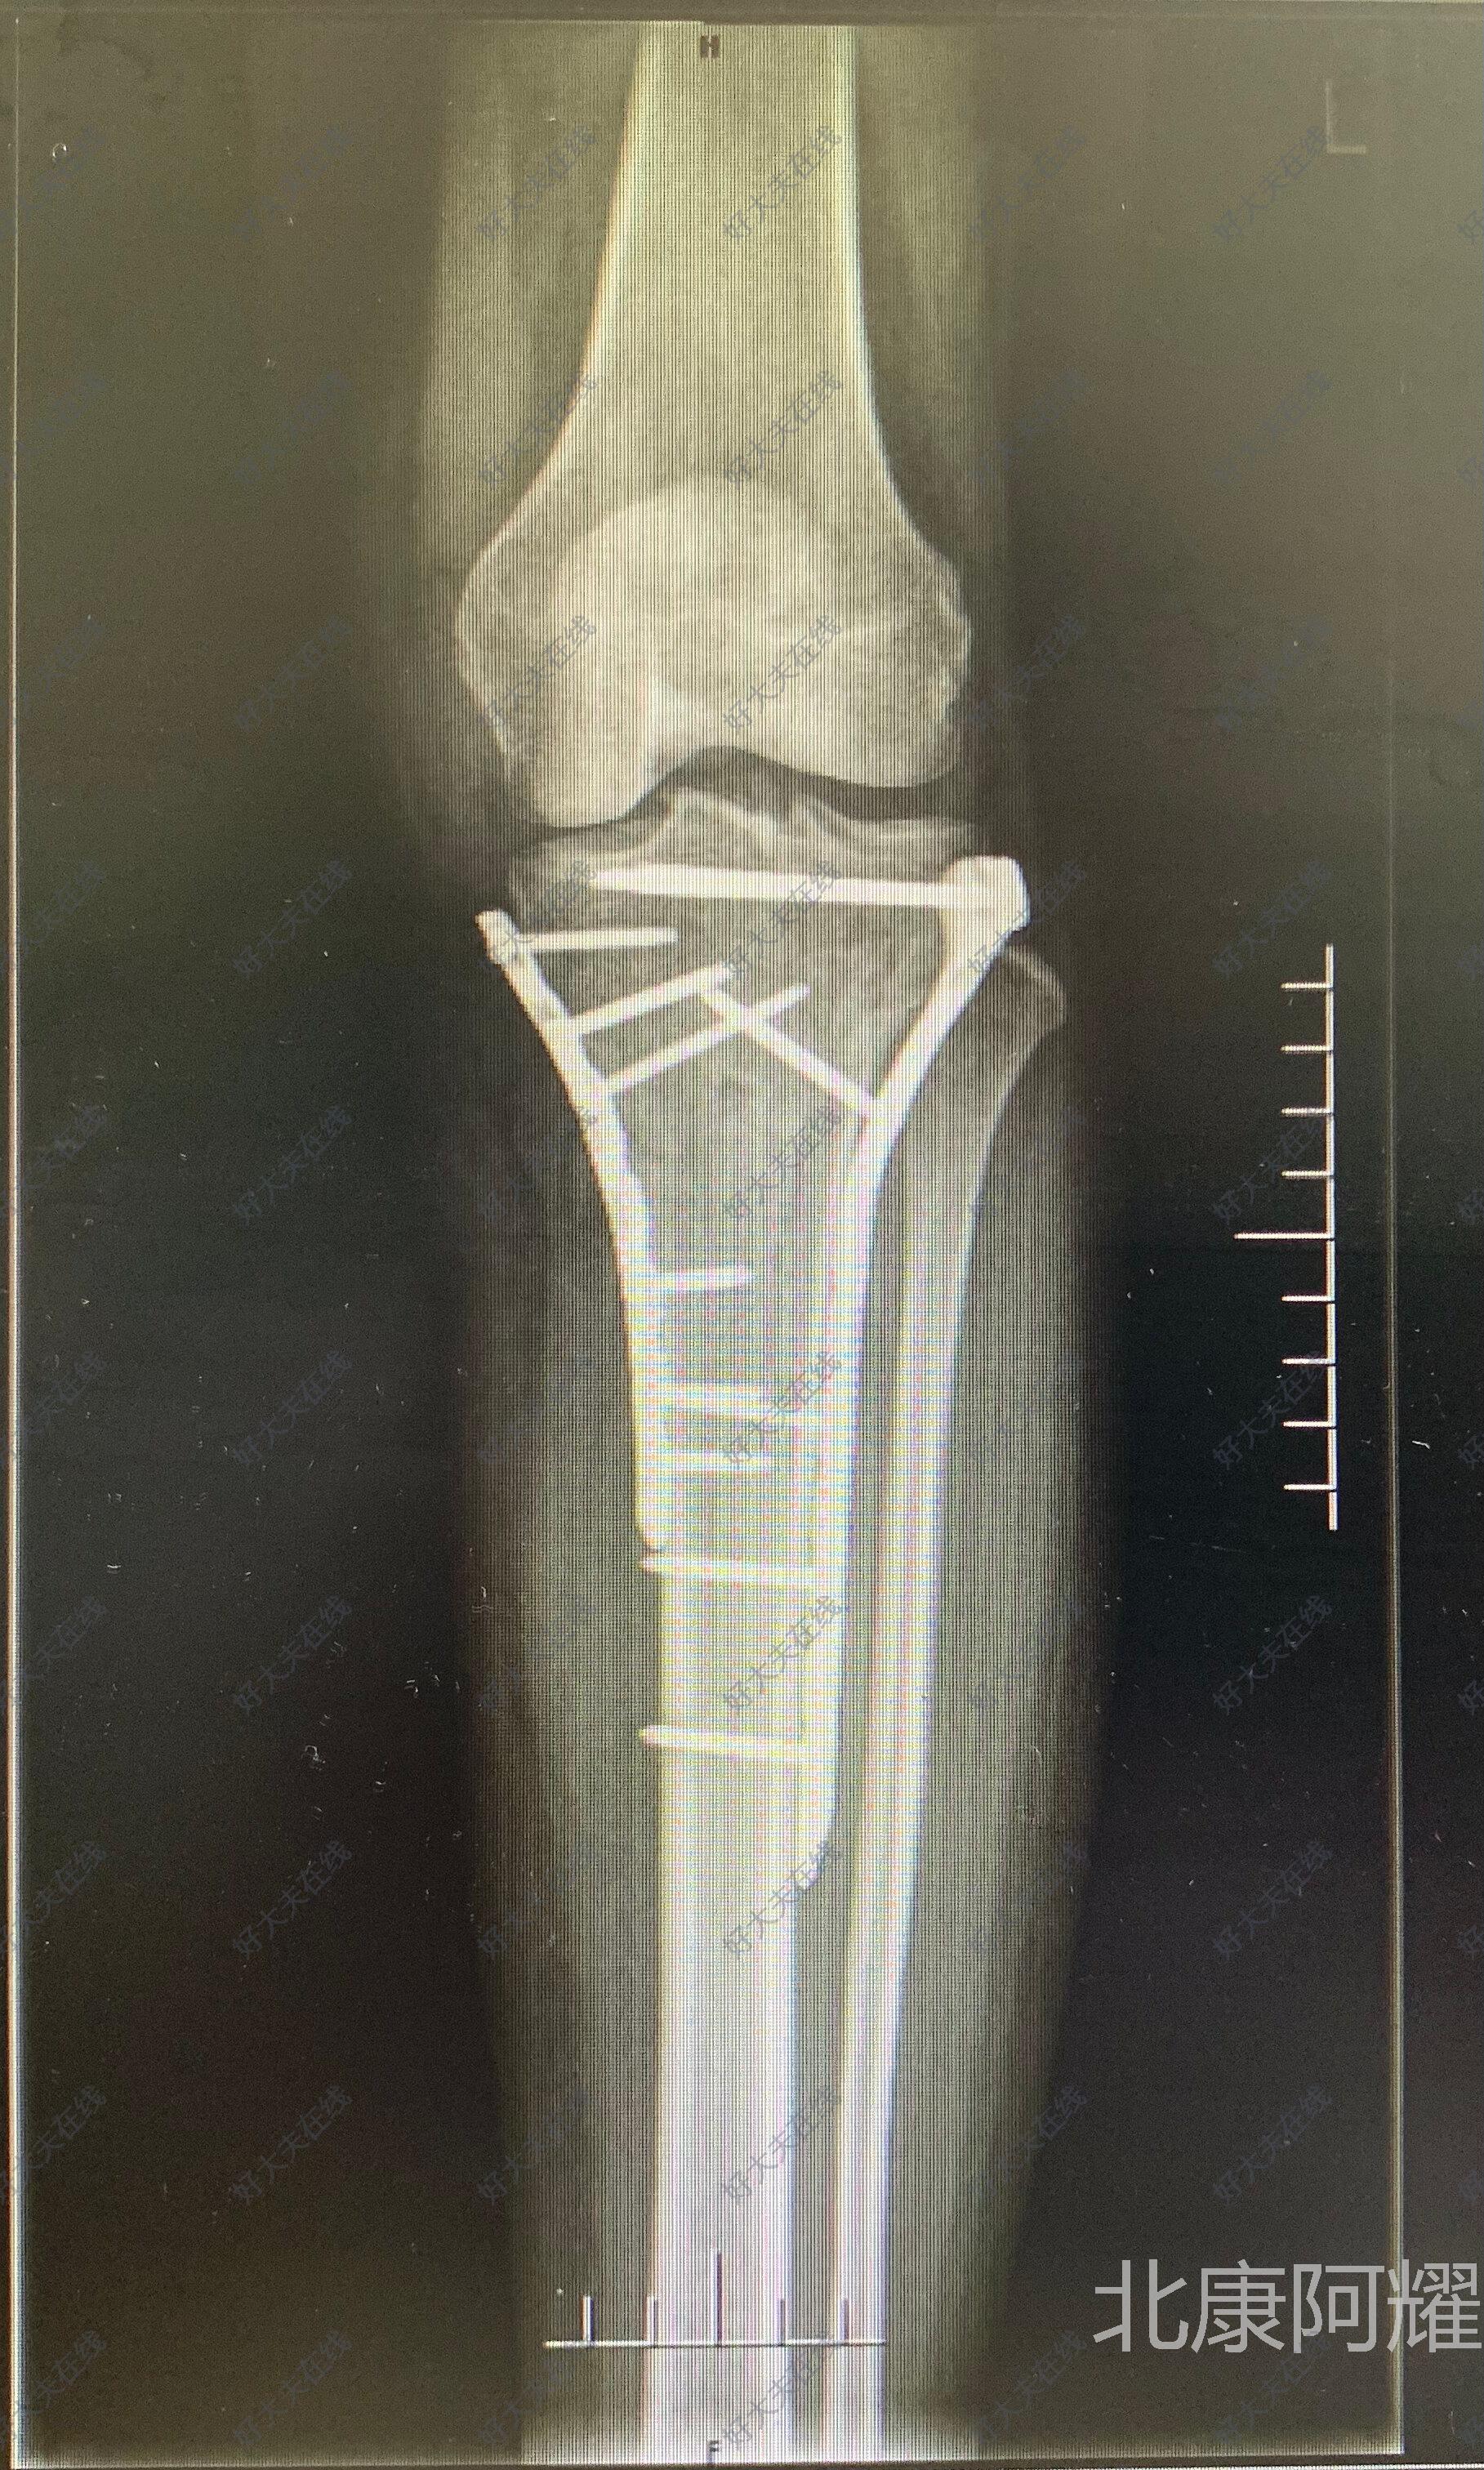

胫骨平台骨折内固定 胫骨平台骨折

胫骨平台骨折 背景 解剖 病理生理学

胫骨平台骨折 百度百科

胫骨平台骨折 治疗